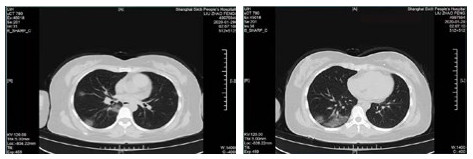

| 图 6 患者,女性,55岁,既往体健,沪籍,无明确武汉流行病学接触史。发热6 d,伴咳嗽,体温39.4℃,伴肌肉酸痛,流感病毒A型IgM阳性,抗柯萨奇病毒IgM阳性,新型冠状病毒核酸检测阴性。肺部CT提示双肺散在磨玻璃结节,部分贴近胸膜。诊断甲型流感病毒性肺炎 Fig 6 Case 6, female, 55 years old, born in Shanghai, was physically healthy, and had no clear history of epidemic exposure of Wuhan. She had fever for 6 days, body temperature was 39.4 ℃, with cough, muscle ache, positive influenza A IgM and anti Coxsackie IgM, negative novel coronavirus nucleic acid test. Lung CT showed ground glass nodules were scattered in bilateral lungs, some of which were close to pleura. She was diagnosed as influenza A virus pneumonia |

| 图 7 患者,女性,36岁,沪籍,有武汉流行病学接触史。发热8 d伴咳嗽,咳痰,有头胀痛,体温38.5℃, 白细胞总数21.8×109/L,淋巴细胞计数10.4%,甲型流感筛查阴性,流感病毒B型IgM阳性,新型冠状病毒核酸检测2次阴性。肺部CT提示双肺多发团片影,实变及磨玻璃结节,伴支气管充气征。诊断乙型流感病毒性肺炎 Fig 7 Case 7, female, 36 years old, born in Shanghai, with a history of epidemic exposure of Wuhan. She had fever for 8 days with cough, expectoration, head pain, body temperature of 38.5℃, total white blood cells of 21.8×109/L, lymphocyte count of 10.4%, negative influenza A virus screening, positive influenza B IgM, and negative novel coronavirus nucleic acid test for twice. Lung CT showed multiple mass shadows, consolidation and ground glass nodule in both lungs, accompanied by bronchiectasis. She was diagnosed as influenza B pneumonia |

| 图 8 患者,男性,20岁,湖北籍,发病前6 d有武汉流行病学接触史,发热,体温39.3℃,有干咳,血白细胞总数及淋巴计数正常,甲型、乙型流感病毒抗原筛查阴性以及其他呼吸道常规病毒筛查阴性,新型冠状病毒核酸检测2次阴性。肺部CT提示左下肺磨玻璃结节,贴近胸膜,可见铺路石征,小叶间胸膜增厚。病因不明 Fig 8 Case 8, male, 20 years old, born in Hubei Province, had a history of epidemic exposure of Wuhan 6 days before the onset of the disease. He had fever with a body temperature of 39.3 ℃, dry cough, normal WBC and lymph count, negative influenza A and B virus screening, and other routine respiratory virus screening, negative novel coronavirus nucleic acid test for twice. Lung CT showed ground glass nodule of the lower left lung, close to the pleura, with paving stone sign and thickening of interlobular pleura. Unknown etiology |